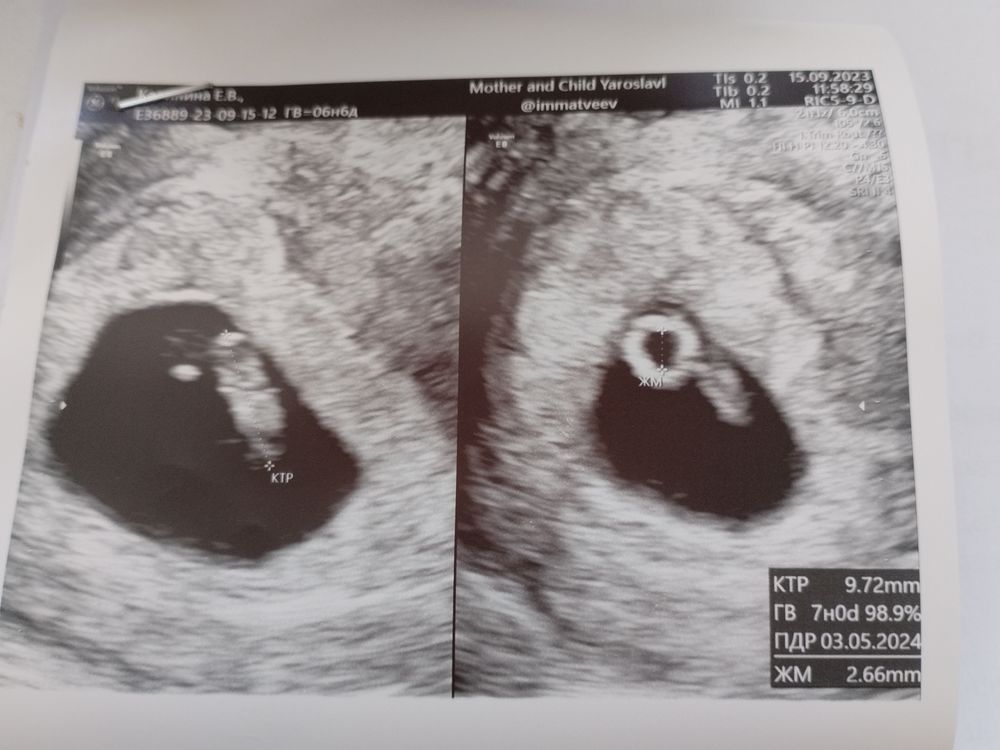

Диана, 🤔 у меня жутко похожее узи сначала он мне эмбрион мерил ( но срок у меня побольше) потом вывернул палку 😱 чуть ли не поперёк влагалища мерил жт слева эмбрион, с права жт у вас на фото как у меня с лева .... 🙏🙏🙏 надеемся что будет все хорошо Изображение

Екатерина, так у вас второе фото справо- там желточный мешочек, его измерили, 2.6мм. А у меня хгч падает, при том что эмбрион есть